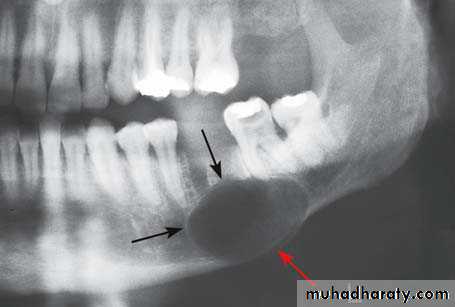

Cysts appear as rounded, radiolucent areasSharply demarcated from normal bone by a thin, radiopaque limiting line of compact bone, this line is not usually present on radiographs of apical granuloma and is often absent or hazy round in infected cysts

Radiographic interpretation

In the maxilla it is sometimes difficult to tell whether a radiolucent area is a cyst or a locule of the maxillary sinus. Therefore it is necessary to compare the radiographs with those of the opposite side, if a similar locule is present the radiolucent area is probably part of the sinus.Finally where doubts still exist, the area may be aspirated and if air, not fluid, is withdrawn it is certainly part of the maxillary sinus.